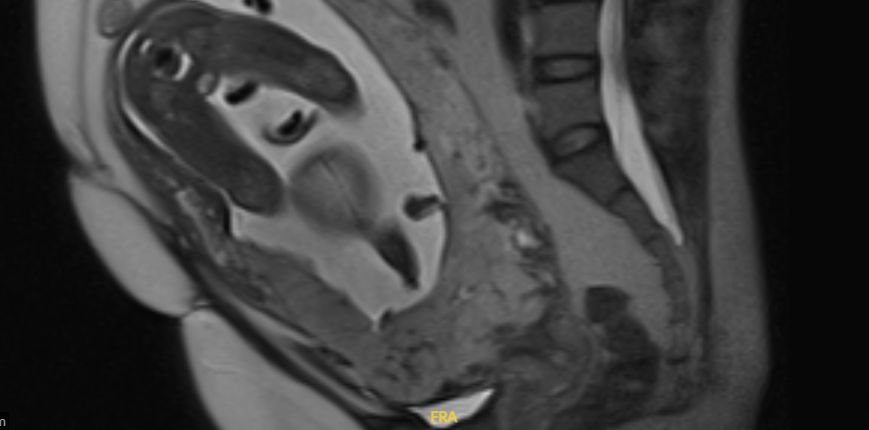

На сроке 27 недель беременности выполнено экспертное УЗИ (врач Мальмберг Ольга Леонидовна): на расстоянии 50 мм от уровня в/зева визуализируется участок плацентарной площадки размерами 50*87 мм, на протяжении которого миометрий не определяется. Серозная оболочка интактна.

На сроке 30 недель беременности МР-признаки врастания плаценты (p. increta), толщина стенки матки неравномерная: на расстоянии около 77 мм от внутреннего зева (где толщина стенки представляется от 4,5 до 9,6 мм с гиперваскуляризацией), на протяжении до 62 мм по длинной оси матки и около 92 мм, билатерально, толщина стенки составляет 1,6 мм. Задняя стенка мочевого пузыря прилежит к измененной стенке матки, дифференцировка мышечного слоя мочевого пузыря не нарушена, достоверных признаков распространения на мочевой пузырь не выявлено).

Установлен диагноз: Беременность 30 недель. Предлежание плаценты. Врастание плаценты (p. increta). Маточная аневризма. Рубец на матке после 2 операций кесарева сечения (2020, 2022 гг.), после миомэктомии (2019).